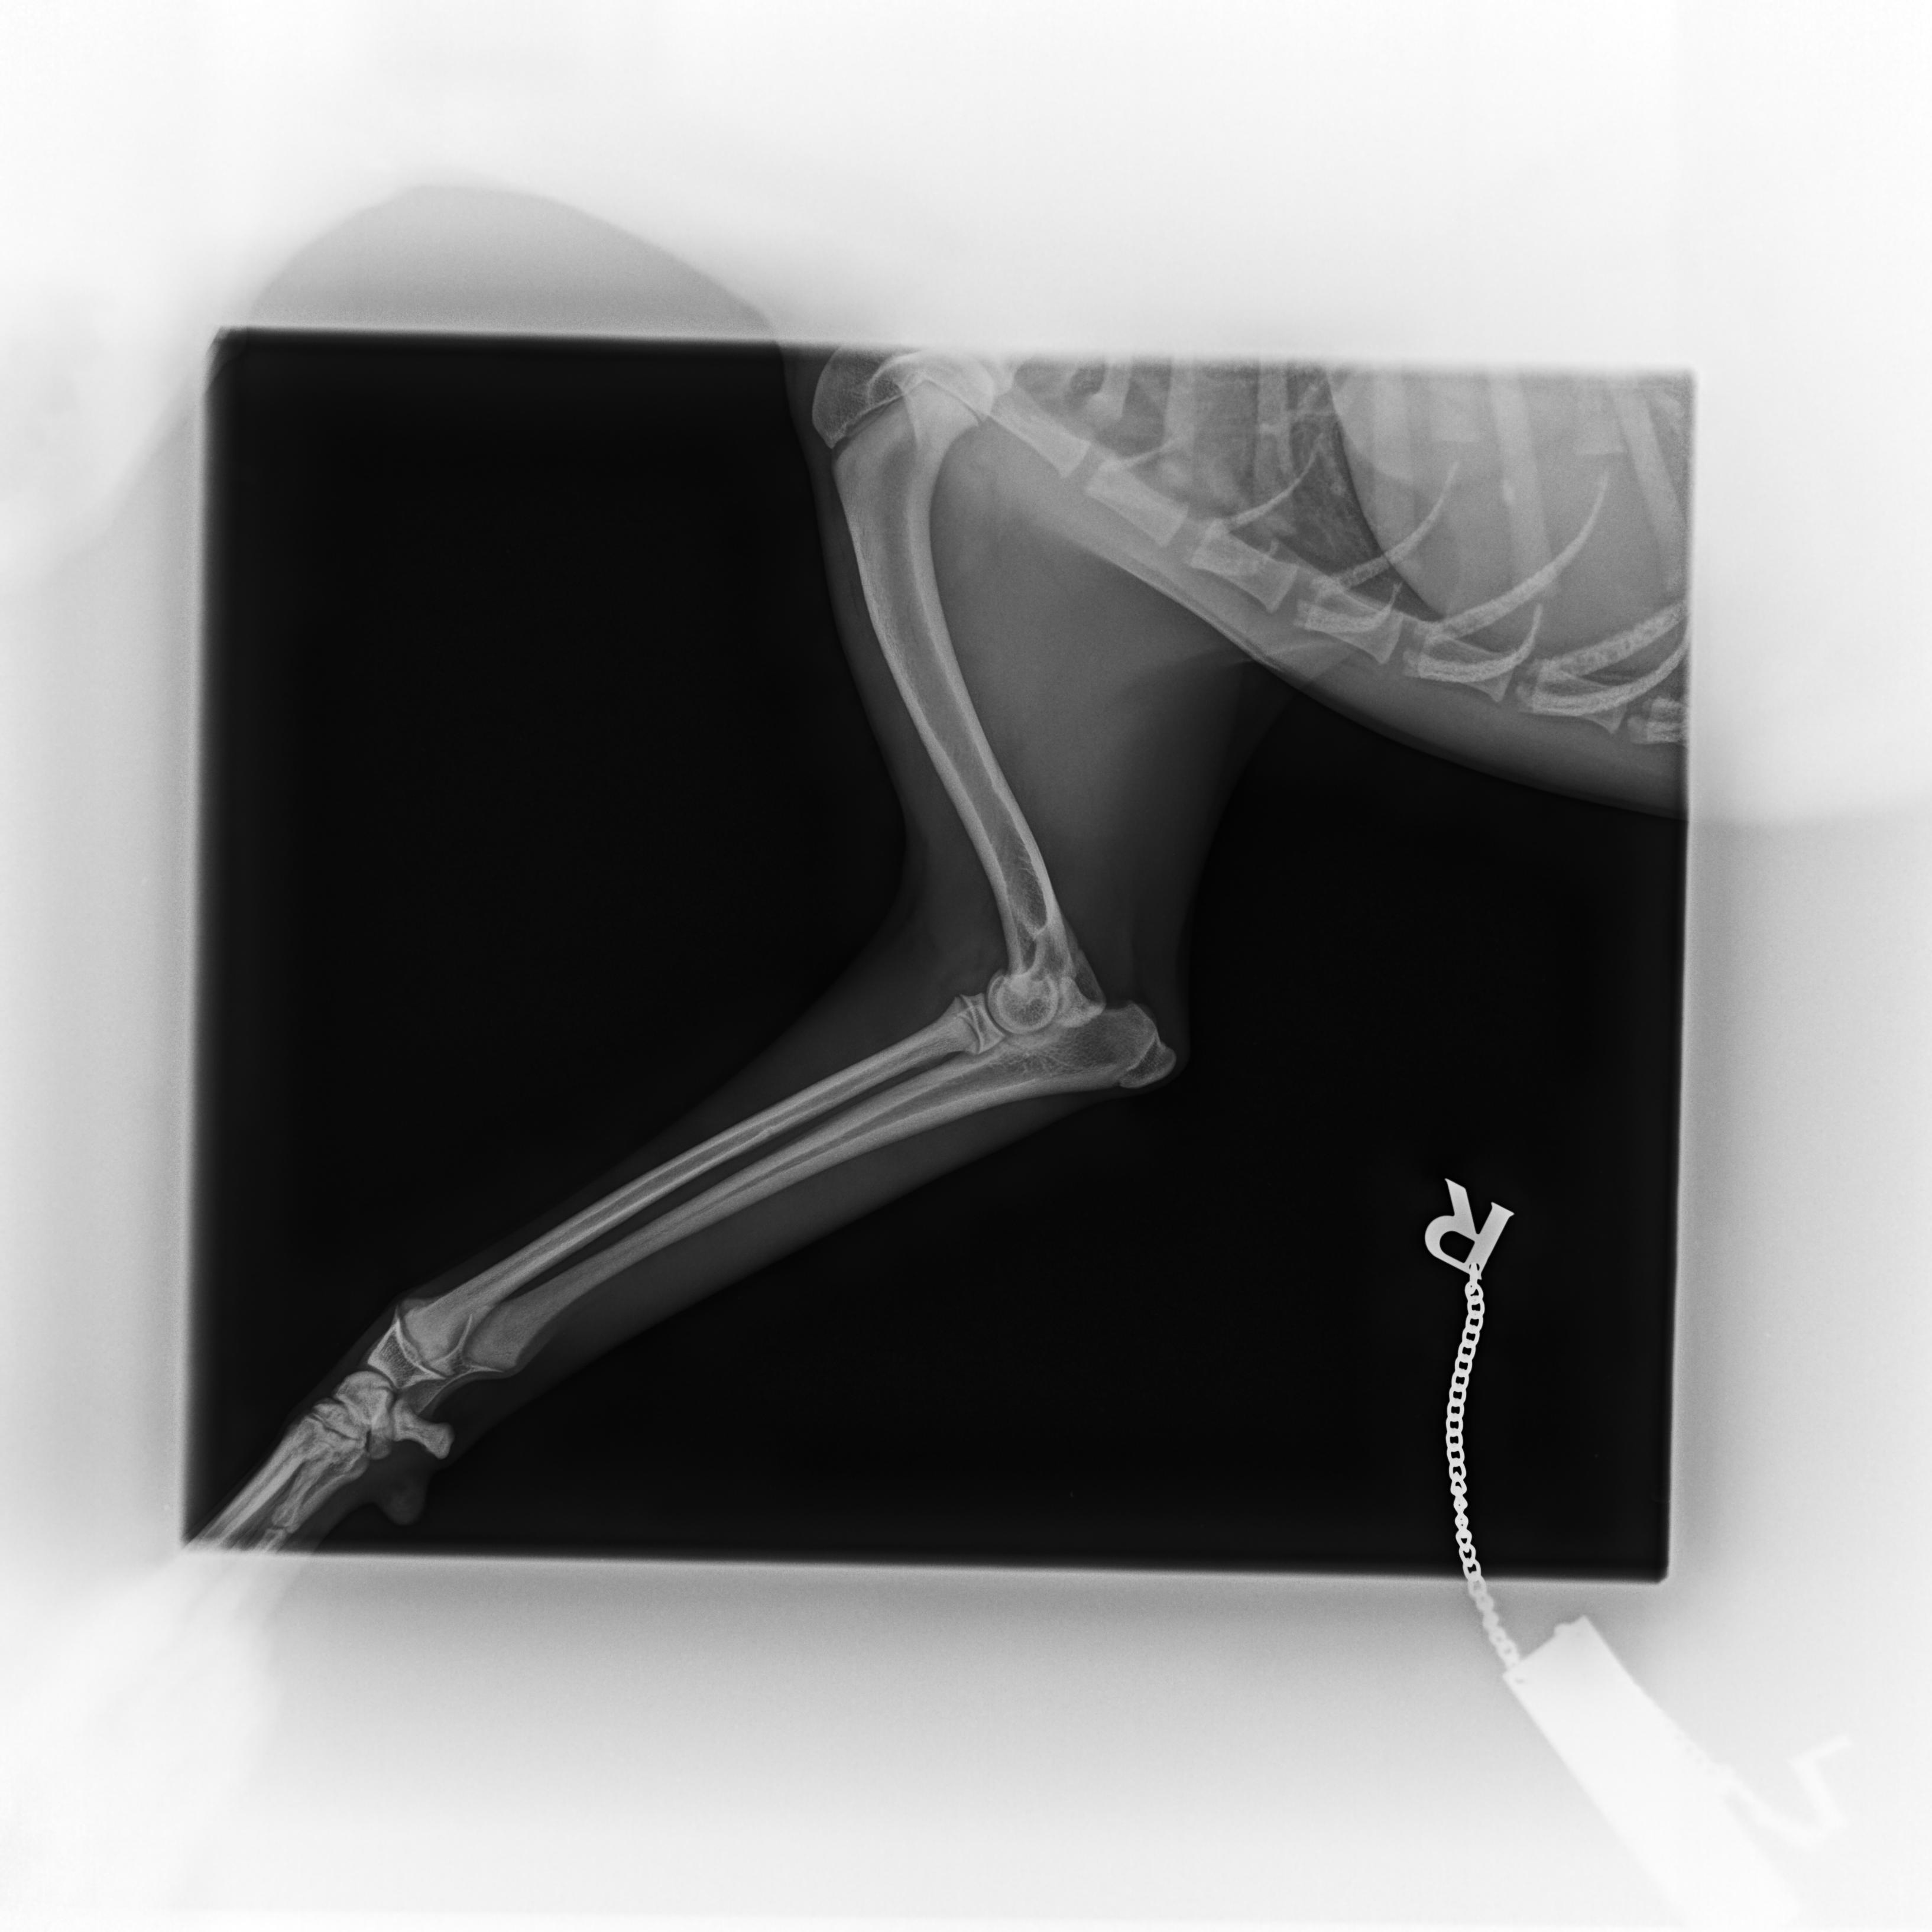

Cushingův syndrom, taktéž nazývaný Hyperadrenokorticismus, patří v současnosti spolu s diabetes mellitus mezi nejčastěji se vyskytující endokrinologická onemocnění psů. Způsobuje ho nadbytek glukokortikoidů, jako Cushingův syndrom pak označujeme soubor příznaků, které onemocnění doprovázejí.